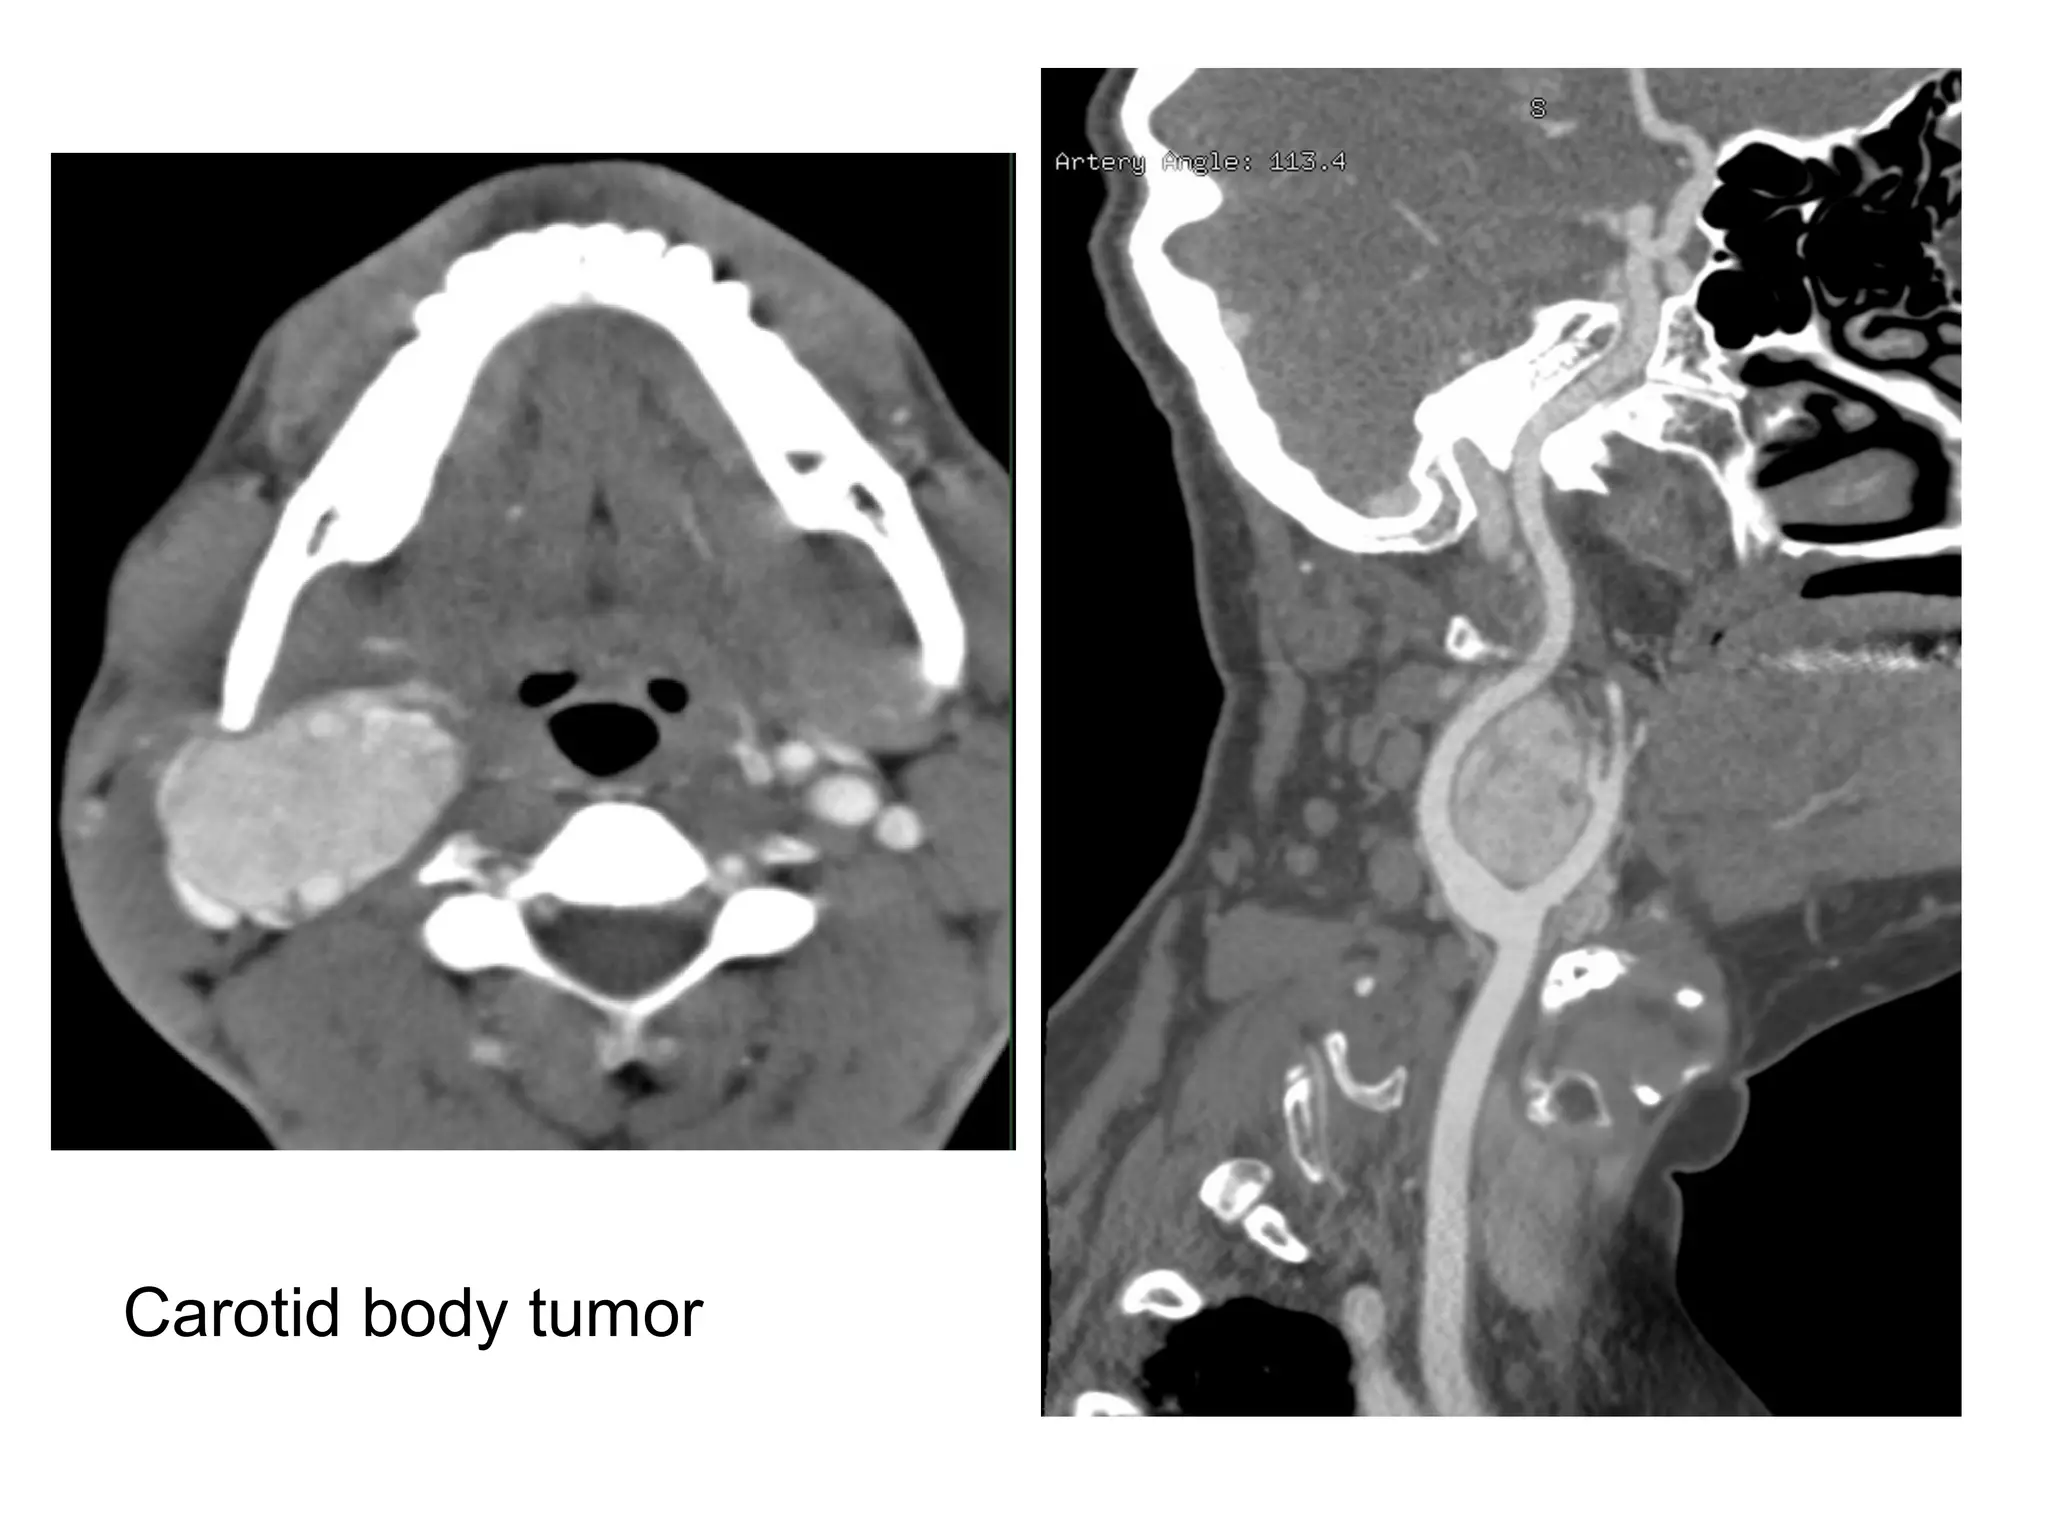

Carotid body tumor

3-Retropharyngeal Space :